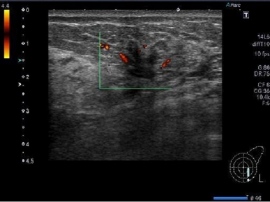

東大などが「人工知能を用いた医療画像と診療情報の統合による高精度な疾患画像判別モデルの開発」を発表。AIを用いて超音波検査画像と診療情報を統合する疾患画像判別モデルを開発。[写真拡大]

1月7日、東京大学のグループと機械学習の先進企業グルーヴノーツが「人工知能を用いた医療画像と診療情報の統合による高精度な疾患画像判別モデルの開発」に成功したことを発表した。画像と数値など異なる種類のデータを同時に学習可能なAIアルゴリズムを用いて腹部超音波検査画像と診療情報を統合する新しい肝腫瘤の疾患画像判別モデルが開発された。従来の画像診断モデルは画像のみを学習させるものであったが、このシステムは画像情報に診療情報を統合することによって判別モデルの精度を飛躍的に向上させることを可能にした。

今回のシステムは慢性肝炎、肝硬変患者から肝癌を早期発見するためのものとして開発されたものだが、現在最も普及している腹部超音波検査では、発見された腫瘤が悪性の腫瘤か良性の腫瘤であるかの質的な鑑別ができず、これを識別するため造影剤を使用したCTやMRIなどによる血行動態的な評価が必要となる。腫瘤の質的な診断が困難であるのは超音波検査を用いた画像は画像の客観的な定量化が困難なためである。

そこで今回用いられた技法が、画像の定量化を行う方法として近年注目されているマルチモーダルによる深層学習だ。腹部超音波検査画像のみで客観的な定量化が可能になれば超音波検査単独で質的な識別が可能となり、CTやMRI検査が不要となり、その際の被爆や医療費の削減に繋げることが可能だ。機械学習で解析すべき情報の種類は画像、数値、音声など多種類に及ぶのが一般的で、それ故に時間がかかる。そこで研究グループは画像と数値など異なる種類のデータを同時に学習することが可能な「マルチモーダル深層学習」の技術を用いて超音波画像に診療情報を統合し同時処理すれば疾患画像の質的な判別が可能となる。